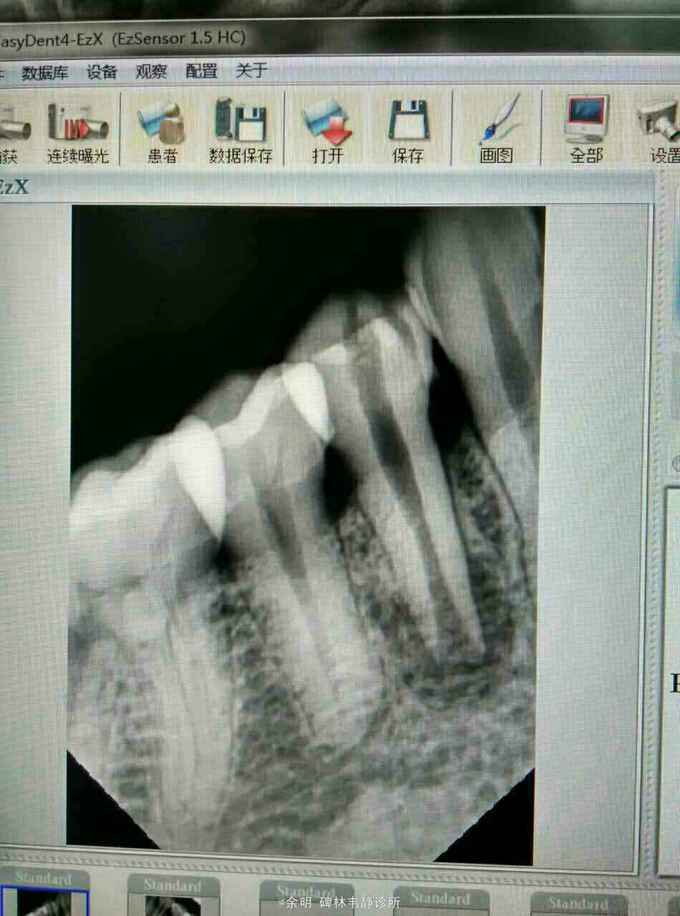

44白色暂封物(去除后可见棉捻),颊侧牙龈可探及瘘管及白色脓性分泌物,叩(+);X线片示:根管口成“喇叭状”,根管中段内可见白色物,根尖阴影。

根尖周炎?根裂?牙内吸收? 处理:44去除暂封料及棉捻,清理髓腔,H2O2.NC冲洗,取出根中白色充填物,隔湿消毒干燥后,手调氢氧化钙暂封 第二次 复诊:44颊侧瘘管未消失,白色脓性分泌物消失,叩(_)。 处理:44去除暂封料,H2O2.NC冲洗,隔湿消毒干燥后,手调碘仿及氢氧化钙暂封。 医嘱:根充后常规医嘱,不适随访。

这个病例还未处理完成,拿出来与大家讨论讨论。 1畸形中央尖一般大都有对称性,检查拍片未见34有中央尖 2牙根纵折早期有冷热痛,咀嚼痛(病人的未有这些症状)(附根纵折的资料), 3根内吸收可见牙冠成粉红色,此病人牙冠未变色 我发出来这个病例:想和大家交流交流,望大家多给宝贵意见,留下这颗牙。